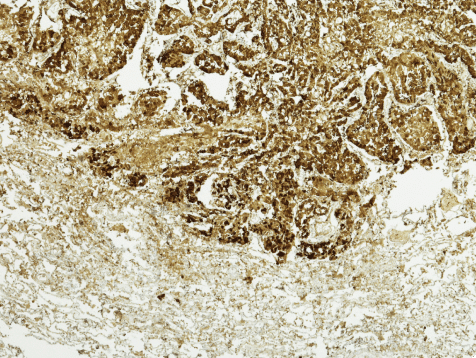

Mesothelioma is a cancer of the mesothelial membranes, the thin membranes surrounding the internal organs. Pleural mesothelioma is cancer of the pleura, which are the mesothelial membranes surrounding the lungs and chest cavity. The visceral pleura surround the lungs, and the parietal pleura line the walls of the chest cavity.